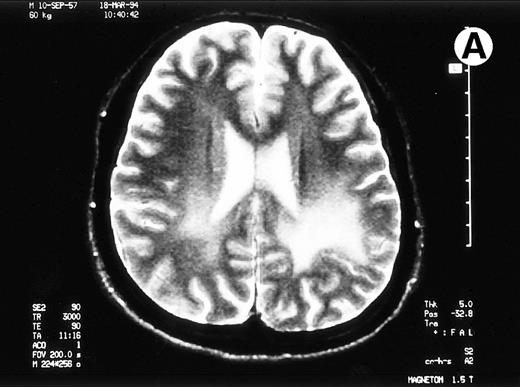

Paths of blight signal on T2-weighted MRI in white matter of brain adjacent bilateral posterior lateral ventricles. (A) On day 526 when we just withheld cyclosporine. (B) On day 698 when chronic GVHD resolved by readministration of cyclosporine.

A 35-year-old man with a chronic myelocytic leukemia in a first chronic phase received an allo-BMT prepared for cyclophosphamide 120 mg/kg and total body irradiation 12 Gy from an HLA-identical sibling in October 1992. Acute GVHD developed in grade III and progressed to an extensive chronic GVHD (cGVHD), which included lichenoid lesions of buccal mucosa, oral dryness, keratoconjunctivitis sicca, and hypolacrimation in addition to skin lesion and liver dysfunction. We treated his cGVHD with 150 mg/d of cyclosporine (CsA) and 10 mg/d of prednisolone (PSL). With dose reduction of CsA from 12 months after allo-BMT, his cGVHD gradually deteriorated. Abrupt seizures, lasting a few minutes, developed on day 491 and day 496 when the patient received 100 mg/d of CsA and 10 mg/d of PSL. Neurological examination revealed no abnormalities. MRI detected the pathes of blight signal on T2-weighted method in white matter of brain adjacent bilateral posterior lateral ventricles (Fig 1A). The eloctroencephalogram revealed epileptic abnormal δ and θ waves on left frontal to central lobe. An examination of cerebrospinal fluid (CSF) revealed as follows: an initial pressure 120 mm H2O, protein 98 mg/dL, sugar 55 mg/dL, chrolide 123 mmol/L, cell count 38/μL with all lymphocytes and negative results in antibodies for cytomegalovirus, herpes simplex virus type-1, and toxoplasma. The concentration of interferon-γ was 0.3 U/L in serum and 1.0 U/L in CSF, which measured by radioimmunoassay kit (Medgenics, Belgium).

To rule out the possibility of CsA neurotoxicity, although the trough levels of CsA ranged from 130 to 170 ng/mL, we withheld CsA at day 526. Despite this attempt, the CNS lesions on MRI did not change, and we subsequently restarted 150 mg/d of CsA at day 537. Thereafter, the CNS lesions gradually resolved with 150 mg/d of CsA and 10 to 20 mg/d of PSL (Fig 1B), coinsident with resolution on the other signs of cGVHD. The seizures never recurred with 600 mg/d of sodium valproate. The patient has now minor CNS lesion and mild signs of cGVHD with 100 mg/d of CsA and with 90% of Karnovsky score at 62 months following allo-BMT.